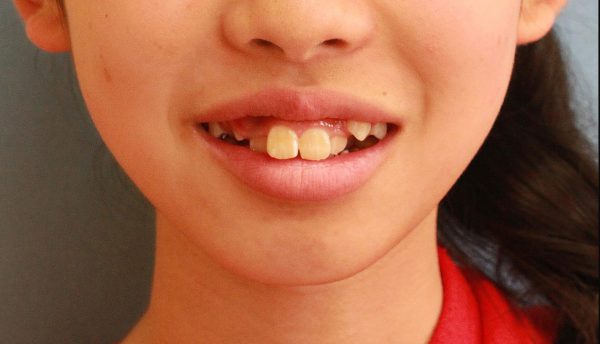

13歳 女性 「 八重歯 出っ歯を 治したい」 ( 上下顎叢生)

13歳の女性 です。

「八重歯と出っ歯をなんとかして欲しい」との事で来院されました。

前歯の段差が激しく、”八重歯”の状態です。

前歯が前に傾斜しているため

”出っ歯”も気になるとの事です。

人と接する時、写真を撮った時などに印象が良くない事を

ご本人以上に お母さまが気にされていました。